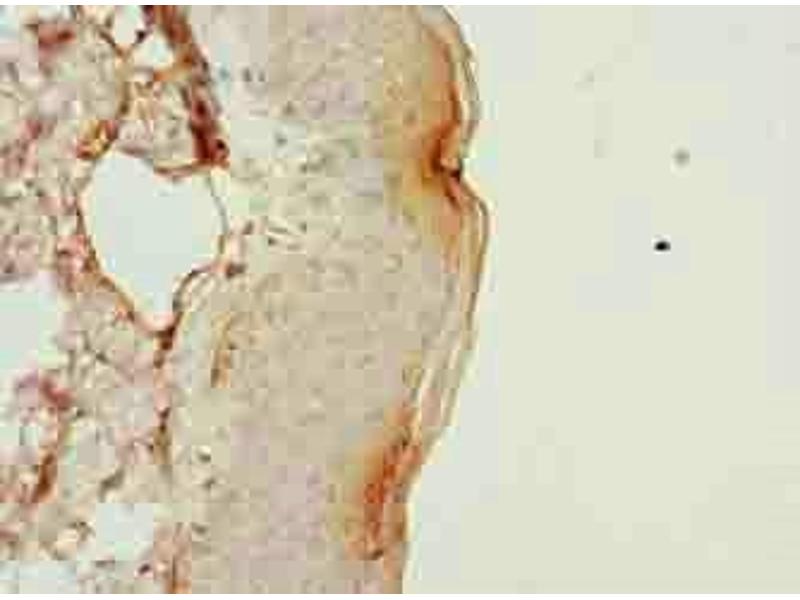

PLGRKT Antikörper (AA 1-147)

Kurzübersicht für PLGRKT Antikörper (AA 1-147) (ABIN7163544)